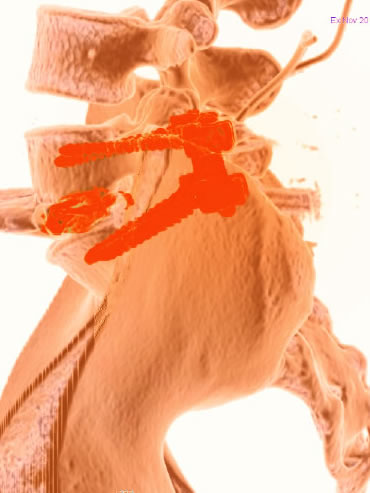

- discectomie antérieure avec mise en place d’une cage

- discectomie antérieure et mise en place d’une prothèse discale

- corpectomie cervicale